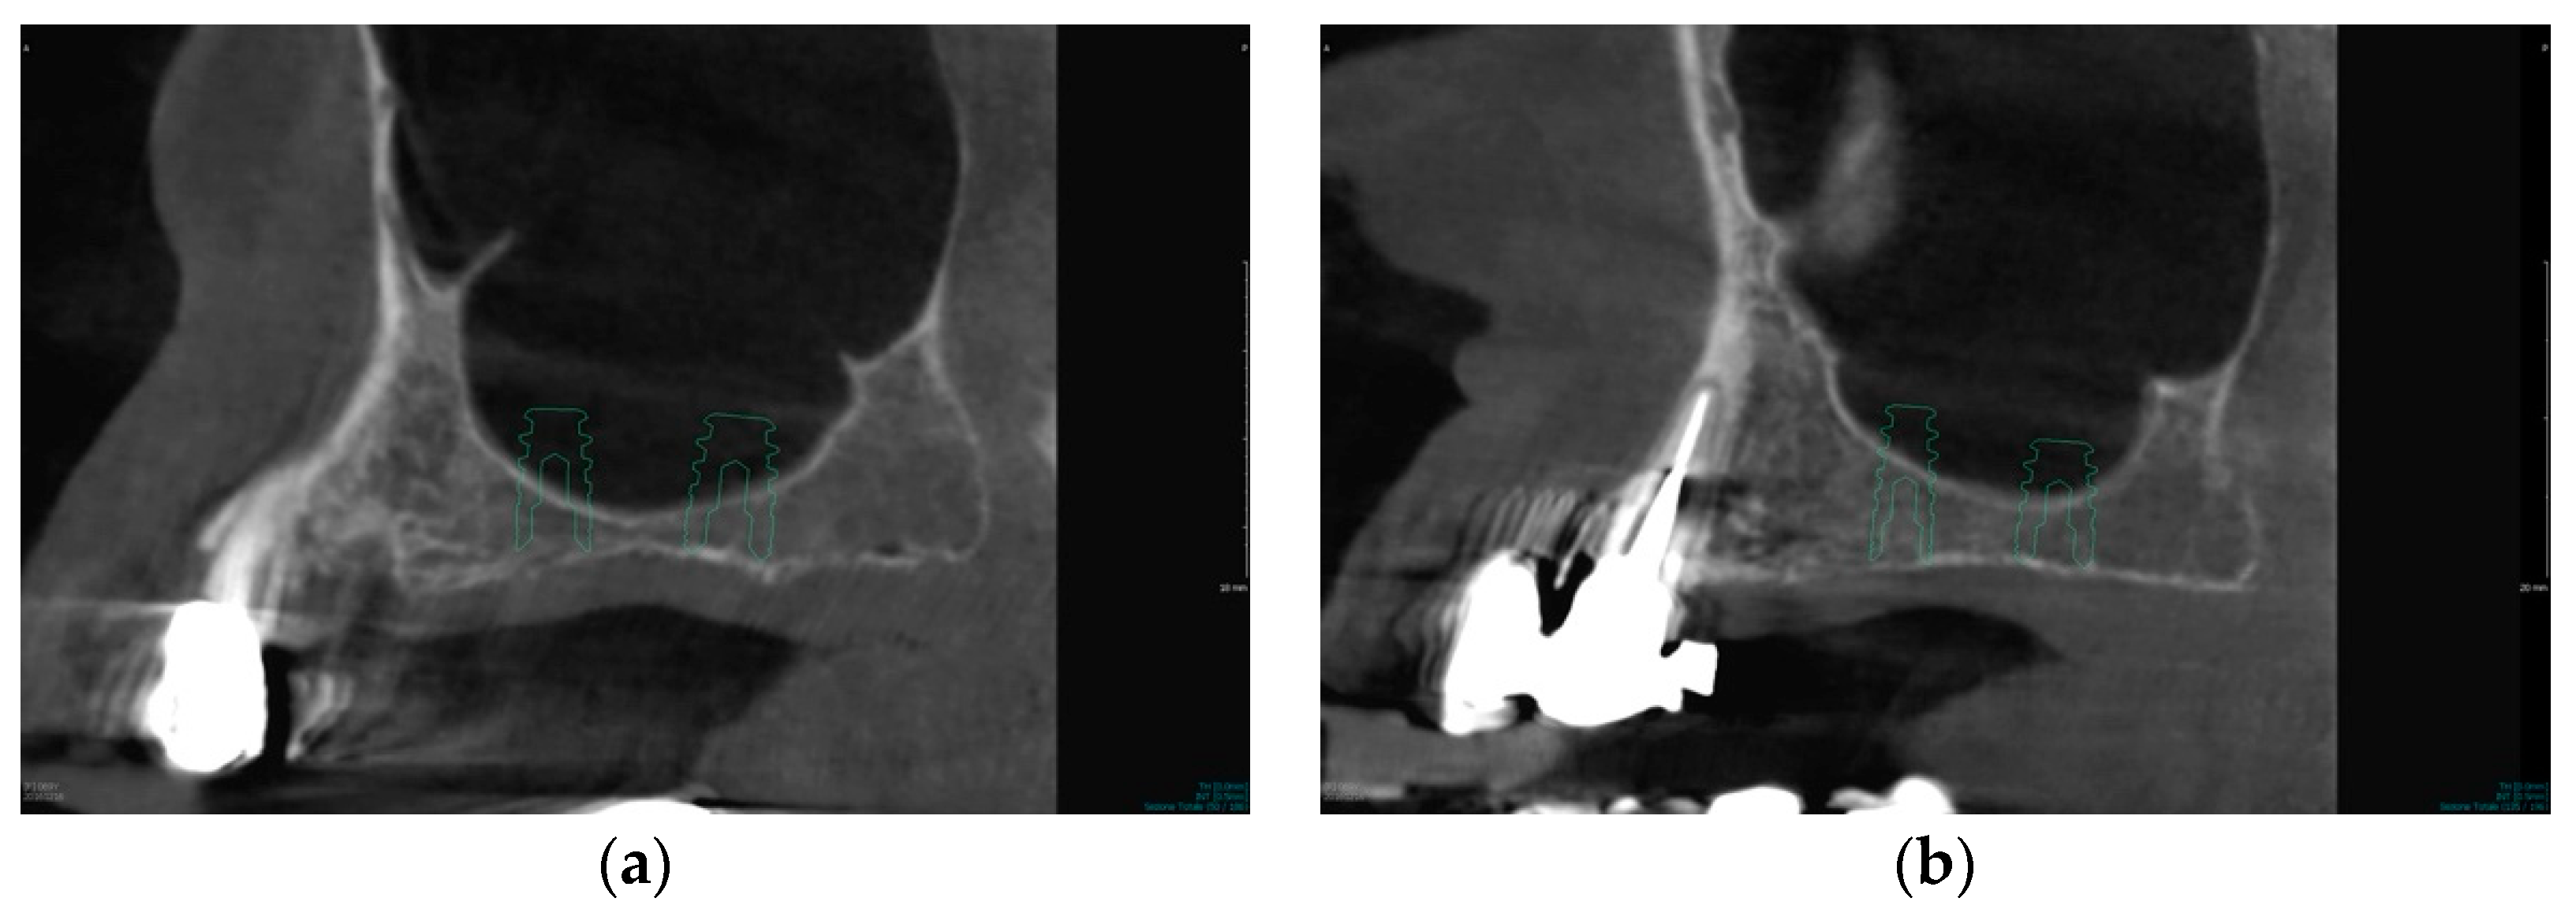

2.6. Case Study